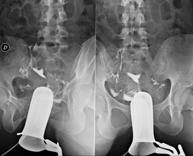

- Cistografía (CUMS)

La cistouretrografía miccional seriada consiste en la obtención de imágenes radiológicas para valorar la anatomía y la función de la uretra y la vejiga con la administración de contraste yodado a través de una sonda vesical.

- Uretrocistografía (Uretro-Cums)

La uretrocistrografía retrógrada y miccional consiste en la obtención de imágenes radiológicas para valorar la anatomía y la función de la vejiga y de la uretra. Se aplica material de contraste a través de una pequeña sonda alojada en la uretra y se obtienen imágenes durante el llenado y vaciado de la vejiga.

- Hipsterosalpingografía (HSG)

Prueba diagnóstica que consiste en la visualización y el estudio del útero y las trompas de Falopio mediante el empleo de rayos X y un medio de contraste. La paciente deberá realizar un tratamiento antibiótico profiláctico. Se recomienda la toma de un sedante suave una hora antes de la prueba.